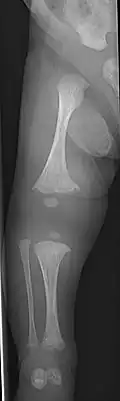

The main symptom of osteogenesis imperfecta is fragile, low mineral density bones; all types of OI have some bone involvement.[5] In moderate and especially severe OI, the long bones may be bowed, sometimes extremely so.[28] The weakness of the bones causes them to fracture easily—a study at the Endocrine Unit at the National Institute of Child Health in Karachi, Pakistan found an average of 5.8 fractures per year in untreated children.[29] Fractures typically occur much less after puberty, but begin to increase again in women after menopause and in men between the ages of 60 and 80.[1]: 486

OI type III causes osteopenic bones that fracture very easily, sometimes even in utero, often leading to hundreds of fractures during a lifetime;[24] early scoliosis that progresses until puberty; dwarfism (a final adult height frequently less than 4 feet or 120 centimetres); loose joints; and possible respiratory problems due to low rib cage volume causing low lung volumes.[5]: 1512

- Type V – Having the same clinical features as type IV, it can be clinically distinguished by observing a "mesh-like" appearance to a bone biopsy under a microscope. Type V can be further distinguished from other types of OI by the "V triad": an opaque band (visible on X-ray) adjacent to the growth plates; hypertrophic calluses (abnormally large masses of bony repair tissue) which form at fracture sites during the healing process; and calcification of the interosseous membrane of the forearm,[50] which may make it difficult to turn the wrist.[1]: 429 Other features of this condition may include pulled elbow, and, as in other types of OI, long bone bowing and hearing loss.[64] Cases of this type are caused by mutations in the IFITM5 gene on chromosome 11p15.5.[64][49] The separation of type V from type IV OI, its clinical type, was initially suggested even before its genetic cause was known, by Glorieux et al. in 2000.[50][65] Type V is relatively common compared to other genetically defined types of OI—4% of OI patients at the genetics department of the Brazilian Hospital de Clínicas de Porto Alegre were found to have it.[66]